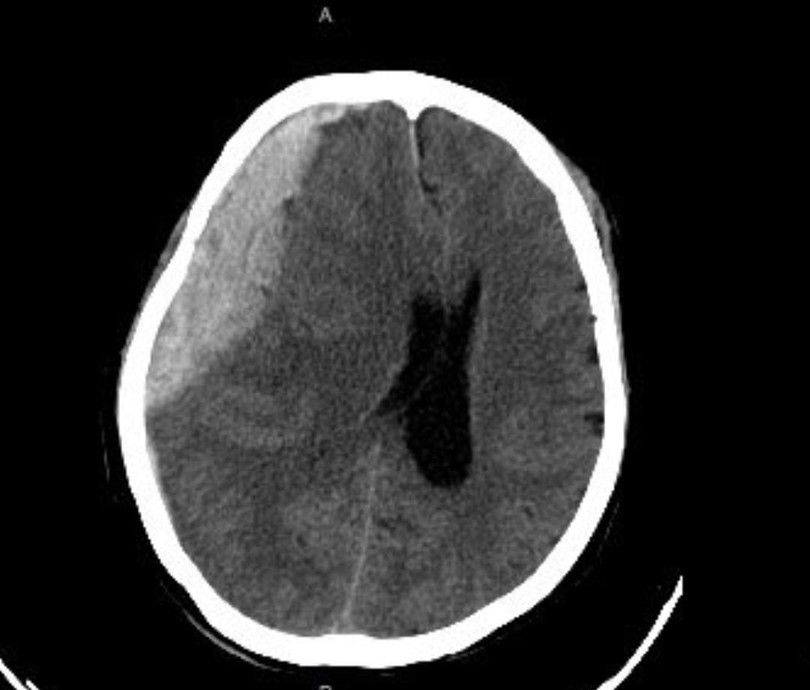

Khối máu tụ lớn trong não của cụ N. (Ảnh - BVCC)

Ngay sau khi bệnh nhân nhập viện, các bác sĩ đã thăm khám và chỉ định chụp cắt lớp vi tính sọ não, đồng thời, làm các xét nghiệm cần thiết. Kết quả chụp cắt lớp vi tính cho thấy, cụ bà có khối máu tụ rất lớn ở nửa đầu bên phải đè đẩy tổ chức não. Các bác sĩ chẩn đoán cụ bà bị máu tụ dưới màng cứng cấp tính bán cầu bên phải.